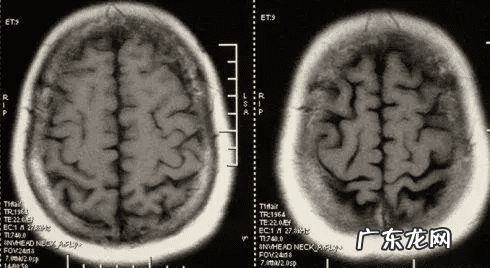

02小脑萎缩是什么?小脑萎缩并不是指某一种疾病,而是退行性病变 。它在老年人中更常见,可能与年龄增长(衰老)或疾病有关 。如果小脑萎缩,人的协调性和平衡能力都会受到影响 。

03小脑萎缩是什么原因引起的?虽然目前还不能完全确定小脑萎缩的所有原因,但是很多因素都会引起小脑萎缩,包括: